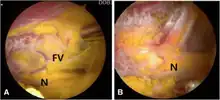

Sciatic nerve entrapment by fibrovascular bands. (a) Endoscopic view of sciatic nerve (N) by fibrovascular bands (FV). (b) Endoscopic view of sciatic nerve (N) after decompression

Surgery involves a nerve decompression with or without muscle resection.[5] The surgery can be performed with external incisions (open surgery) or endoscopically. Endoscopy allows for complete sciatic nerve visualization and access for decompression in the extrapelvic gluteal space.[1] The goal of surgery is to restore normal nerve kinematics and nerve conduction. During surgery this is measured by nerve conduction studies and electromyography, as well as observing the sciatic nerve mobility while the patients hips are moved.[1][2] This testing can be done before and after the decompression to verify improvement before concluding the surgery.